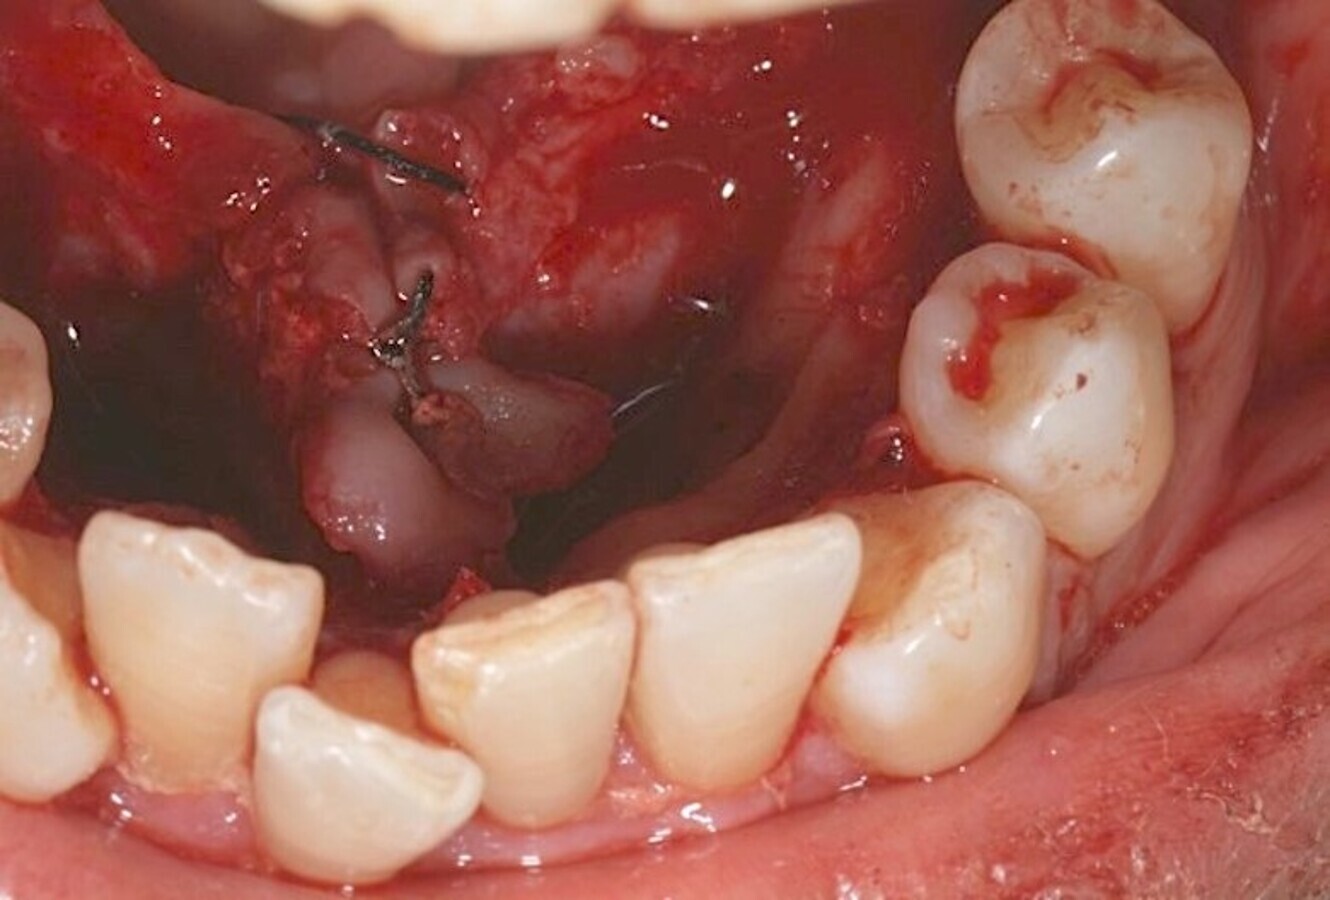

Algunos láseres como los de erbio, y en mi día a día en concreto el de Er,Cr:YSGG (Waterlase), permiten realizar un corte óseo quirúrgico muy preciso (Figuras 9-13), que transmite un daño térmico mínimo a los tejidos adyacentes9.

El láser Er,Cr:YSGG de alta potencia permite realizar cortes óseos quirúrgicos muy precisos (ver Figuras 9-13).

Figura 9.

Figura 10.

Figura 11.

Figura 12.

Figura 13. Las figuras 9-13 permiten observar un corte óseo quirúrgico muy preciso realizado con láser de erbio que produce un daño térmico mínimo en los tejidos adyacentes.